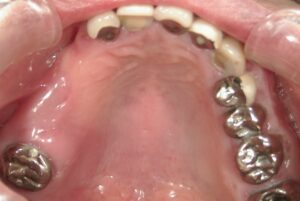

画像の左側には4本分歯がありません。

さらに奥歯も良い状態ではないので抜歯しました。

このように奥歯にしっかりとインプラントが

入りました。

歯が増えています。